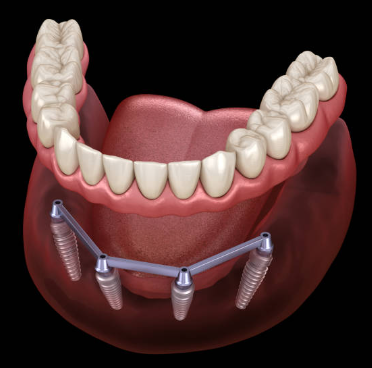

임플란트는 크게 세 부분으로 나뉘며, 치아 뿌리를 대신하는 구조물인 임플란트 (인공치근), 그 위에 체결을 하는 보철기둥 (지대주), 마지막으로 그 위에 씌우는 보철물 (크라운)이 있습니다.